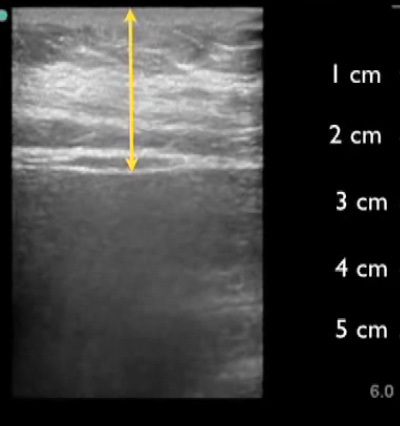

Abdominal no bowel